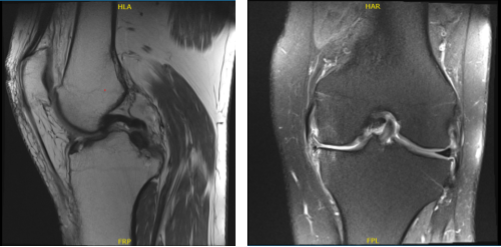

The patient is a 57 year-old woman who has been seen several times for pain on the inner side of her left knee. We had talked about therapy alternatives. Nonsurgical treatment in the form of physical therapy and anti-inflammatory medicines did not benefit the patient. An MRI was performed, which revealed a tear in the medial meniscus as well as suspected involvement of the root of the left knee.

MRI-3T Left knee non-contrast

MRI-3T: left knee non-contrast.